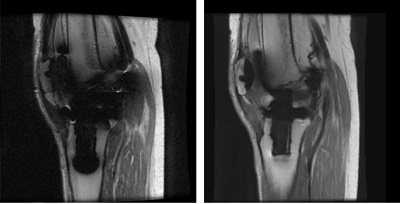

Figure 3. Ring-like artifact in MAVRIC SL image

Figure 4. Ghost-like artifact in MAVRIC SL image